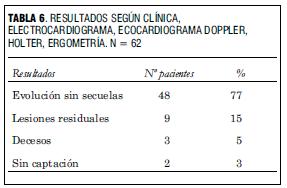

El seguimiento realizado luego del alta hospitalaria a los 60 pacientes ha mostrado que en 48 (77%) la evolución ha sido excelente, con buen crecimiento y desarrollo, permaneciendo en ritmo sinusal, con buena función de ambos ventrículos, sin insuficiencias valvulares ni estenosis supravalvulares significativas, sin requerimiento de procedimientos invasivos adicionales (figura 5).

Analizando en forma global dicho período de seguimiento hemos tenido una excelente evolución, estando la mayoría de los pacientes en el momento actual asintomáticos (54 pacientes, 92%) (tabla 6) (7-10).